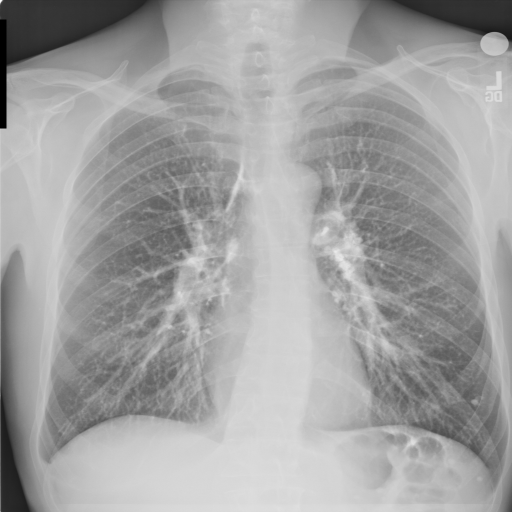

3.3 Applicability to Real X-ray

In order to explore the applicability of our algorithm to real X-ray and to examine whether the enhancement scheme introduces artifacts detrimental to CAD detection performance, we chose to perform the lung enhancement algorithm as a preprocessing step on nodule and mass CAD input images.

To accomplish this, we trained and tested a CheXNet [5] based network on 67,313 images released in ChestX-ray14 dataset(subset of PA images). In Figure 8 we show the results of the enhancement on an image from NIH ChestX-ray14 dataset [4]. The architecture we chose was a DenseNet-121 based network, with 512×512512512512\times 512 input size. Network weights were initialized with pretrained ImageNet weights and training was performed independently for enhanced images and non-enhanced images.

The dataset was split to 44,971 training, 11,245 validation and 11,097 test images. Results are given on the official test set in terms of average precision (AP) for the labels mass and nodule. We see a moderate increase in AP scores for the mass detection task (Table 2).

Refer to caption

(a)

(b)

(c)

(d)

Figure 8: Enhancement result on NIH ChestX-Ray14 image. One network was trained on the original X-ray and a second network was trained on the enhanced X-ray (a) Original X-ray (b) Enhanced X-ray (c) Zoom (d) Zoom -Enhanced